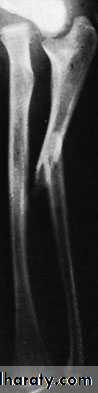

The fracture is usually quite obvious like pain swelling and deformity, but the pulse must be felt and the hand examined for circulatory or neural deficit. Repeated examination is necessary in order to detect an impending compartment syndrome.X-RAY

Both bones are broken, either transversely and at the same level or obliquely with the radial fracture usually at a higher level. In children, the fracture is often incomplete (greenstick) and only angulated.X-RAY